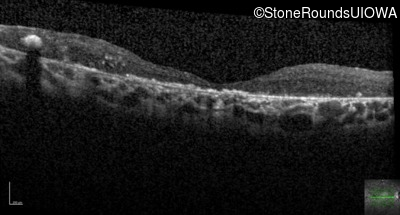

Optical Coherence Tomography - Right - 20/400 sc

Exemplar / OCT Stack